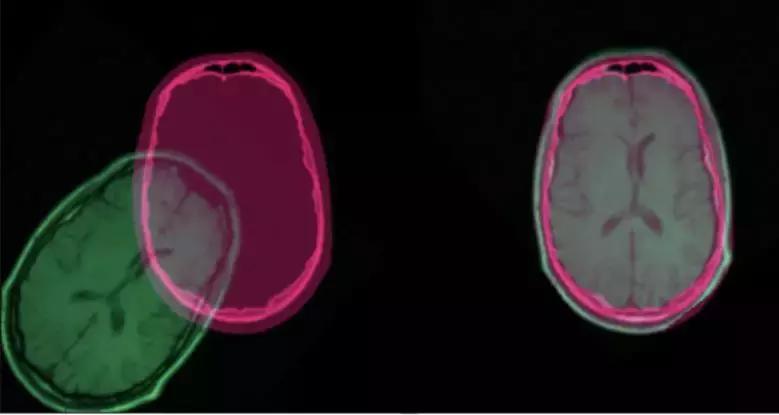

图像配准有很广泛的应用:只要我们面对的任务需要比较相同场景的多张图片,它就是必不可少的。它在医学影像、卫星图像分析以及光流领域都是很常用的。

经过配准后的 CT 扫描和核磁共振图像